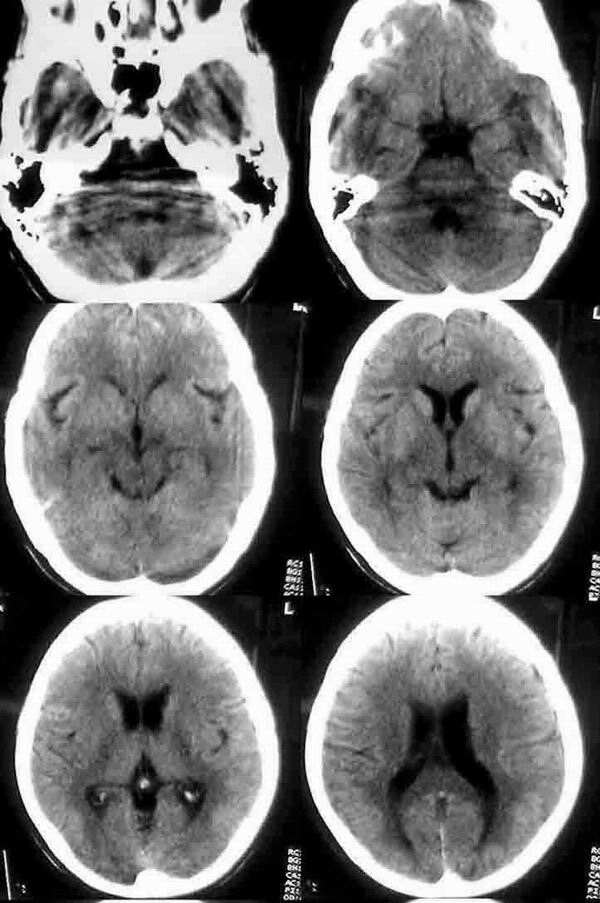

女 57岁 头晕壹月 呕吐半月

平扫:仅见顶叶两个结节状高密度影.边缘清楚.ct值66.1hu 周围无水肿带

增强:脑内广泛多发结节影.多位于皮质和皮髓质交界区,强化明显.ct值达86.5hu.